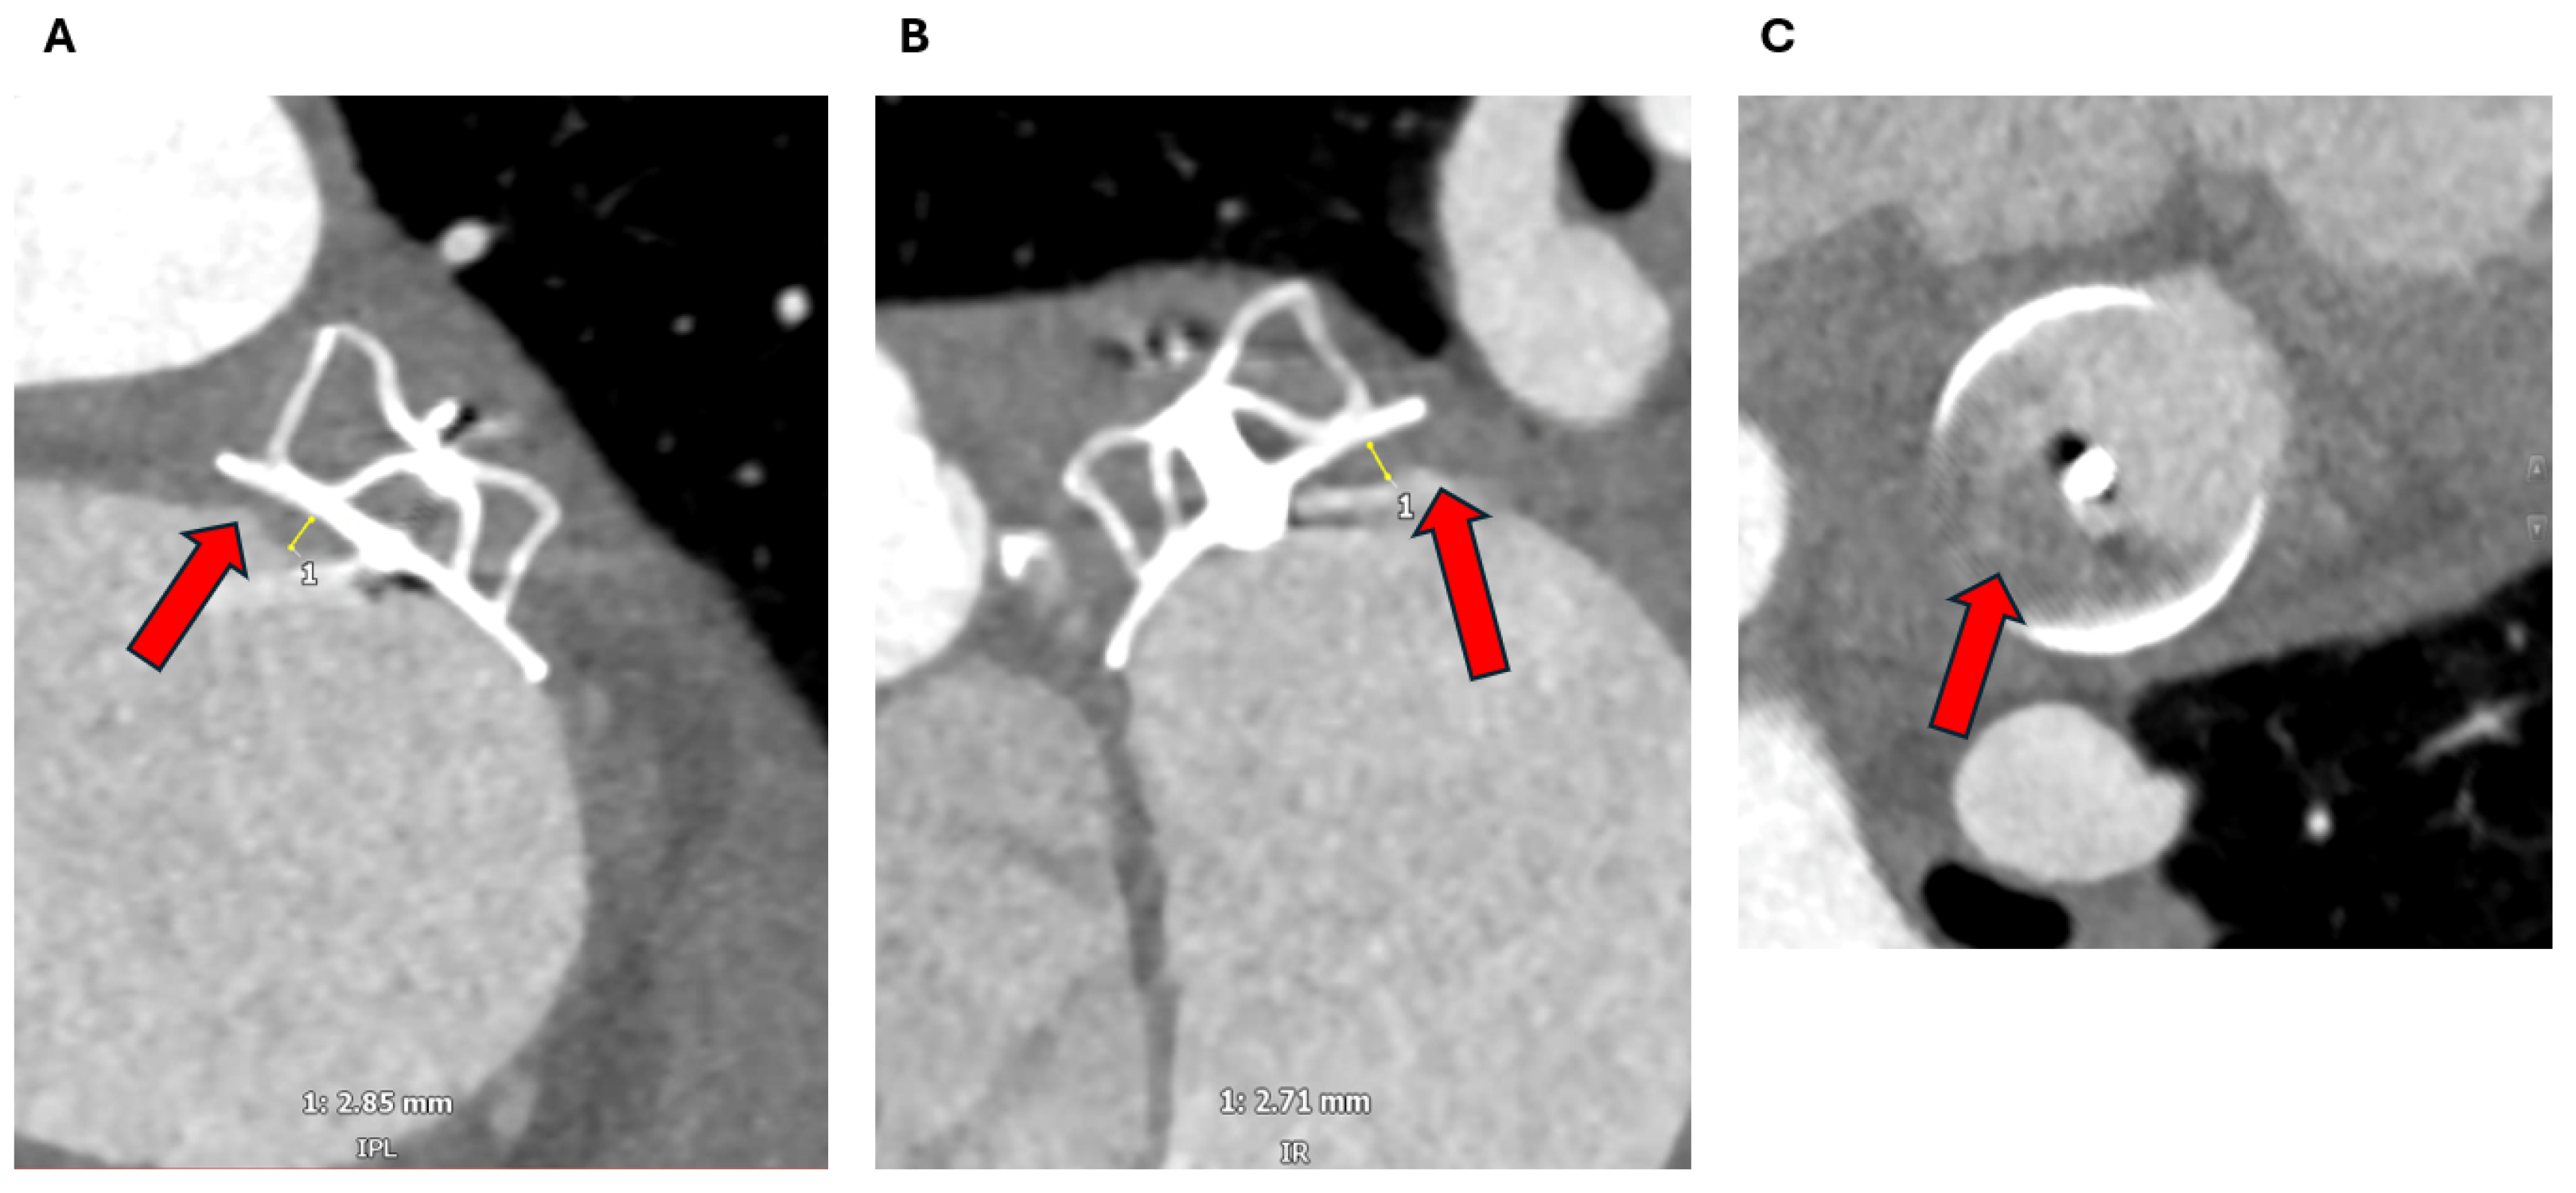

2.1.3. Assessment of the Inter-Atrial Septum

2.1.4. Other Anatomical Considerations

3.1. Device Position and Embolization

3.2. Peri-Device Leaks